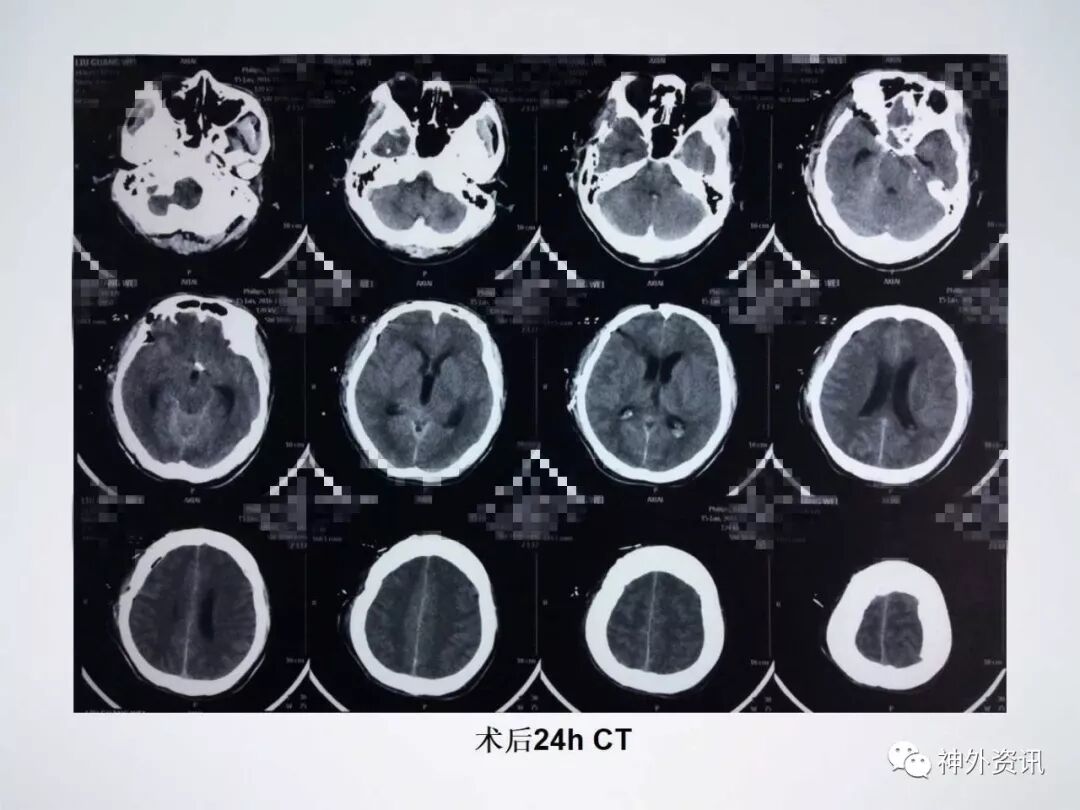

患者缘于10天前无明显诱因突发头痛伴呕吐,于当地医院就诊查头部CT提示:SAH;遂于当地医院予以保守治疗,其后症状逐渐好转;于发病9天后突然出现右眼眼睑下垂及右眼视物不清,遂到河北医科大学第二医院东院区就诊。头部CT提示未见明显出血;头部CTA提示:右侧后交通动脉动脉瘤及左侧脉络膜前动脉动脉瘤。

经右侧翼点入路夹闭

右侧后交通及左侧脉络膜前动脉动脉瘤